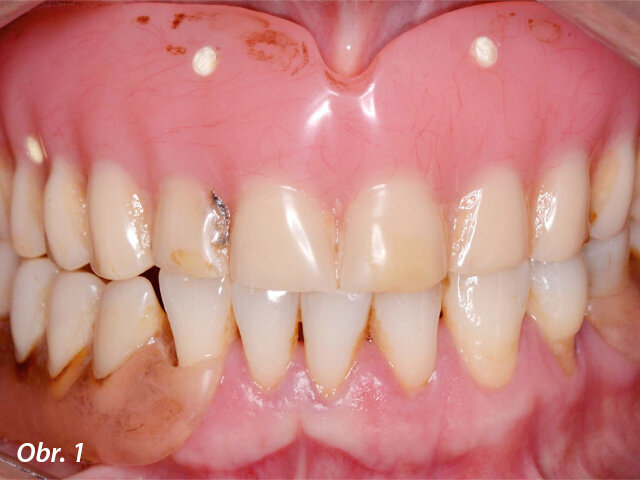

Pacientka se dostavila na naši kliniku se snímatelnou náhradou v horní čelisti (obr. 1), která vykazovala nízkou stabilitu a nevyhovující žvýkací funkci. Pacientka si stěžovala i na estetiku, ale funkční aspekt byl pro ni rozhodující. Po klinickém vyšetření (obr. 2–3) a CBCT analýze jsme naplánovali zavedení šesti implantátů Straumann BLX jako oporu pro fixní můstek v rozsahu celého oblouku (obr. 4). Provizorní můstek byl vyroben před zavedením implantátů. K provedení statické řízené operace byla vytištěna chirurgická šablona.

Prostřednictvím softwaru coDiagnostiX jsme zjistili, že je k dispozici dostatek kosti pro zavedení implantátů, kromě dvou oblastí, do nichž bude nutno transplantovat kostní štěp (obr. 5, 6). Bylo naplánováno celkem šest implantátů s adekvátním rozložením po oblouku, které vytvoří podpěru pro žvýkací síly a zabrání jednostranné zátěži (obr. 7). Zavedení implantátů bylo naplánováno za použití chirurgické šablony (obr. 8) a na implantáty měla být hned po chirurgickém zákroku našroubována provizorní náhrada – jednalo se tedy o protokol okamžitého zatížení.